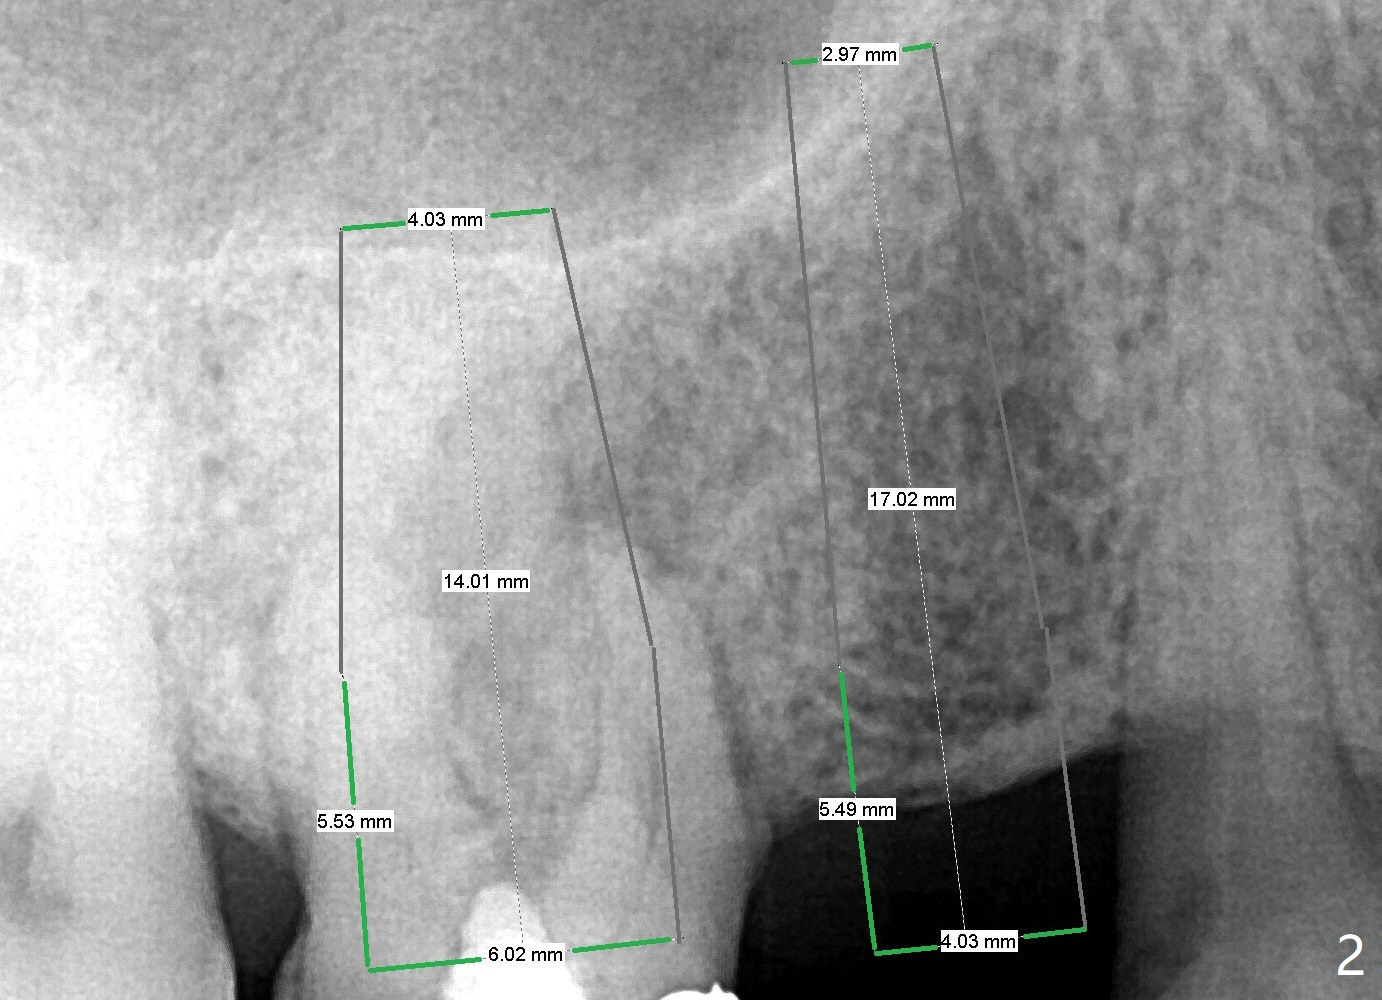

A 67-year-old man used to have a 3/4 cantilever bridge, which is dislodged (Fig.1). The anchor tooth has a buccal fistula with apparent furca perforation and mesiobuccal periapical radiolucency (<). Prior to extraction, the tooth will be used as a surgical guide for implant placement at #4 (Fig.2). Since the bone density at #4 seems to be low (*), bone expander kit will be used.